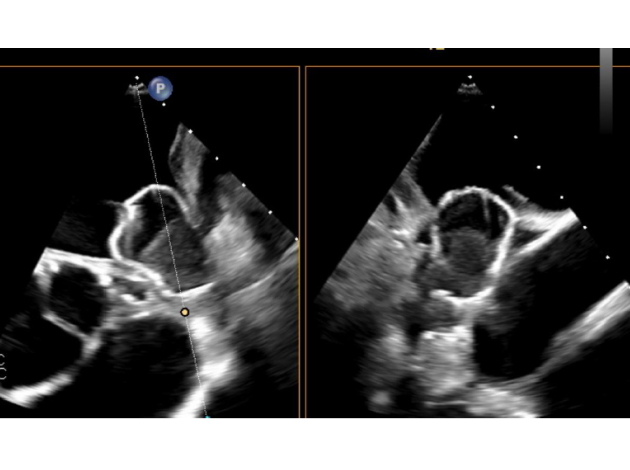

徐脈性不整脈に対しては、従来型ペースメーカに加え、リードレスペースメーカ(Micra™)を導入しており、高齢者やリード感染リスクのある患者に対して有用な選択肢を提供しています。加えて、脳梗塞予防を目的とした左心耳閉鎖術(Watchman™など)も施行可能であり、抗凝固療法が困難な患者への代替治療としての役割も果たしています。

Watchman